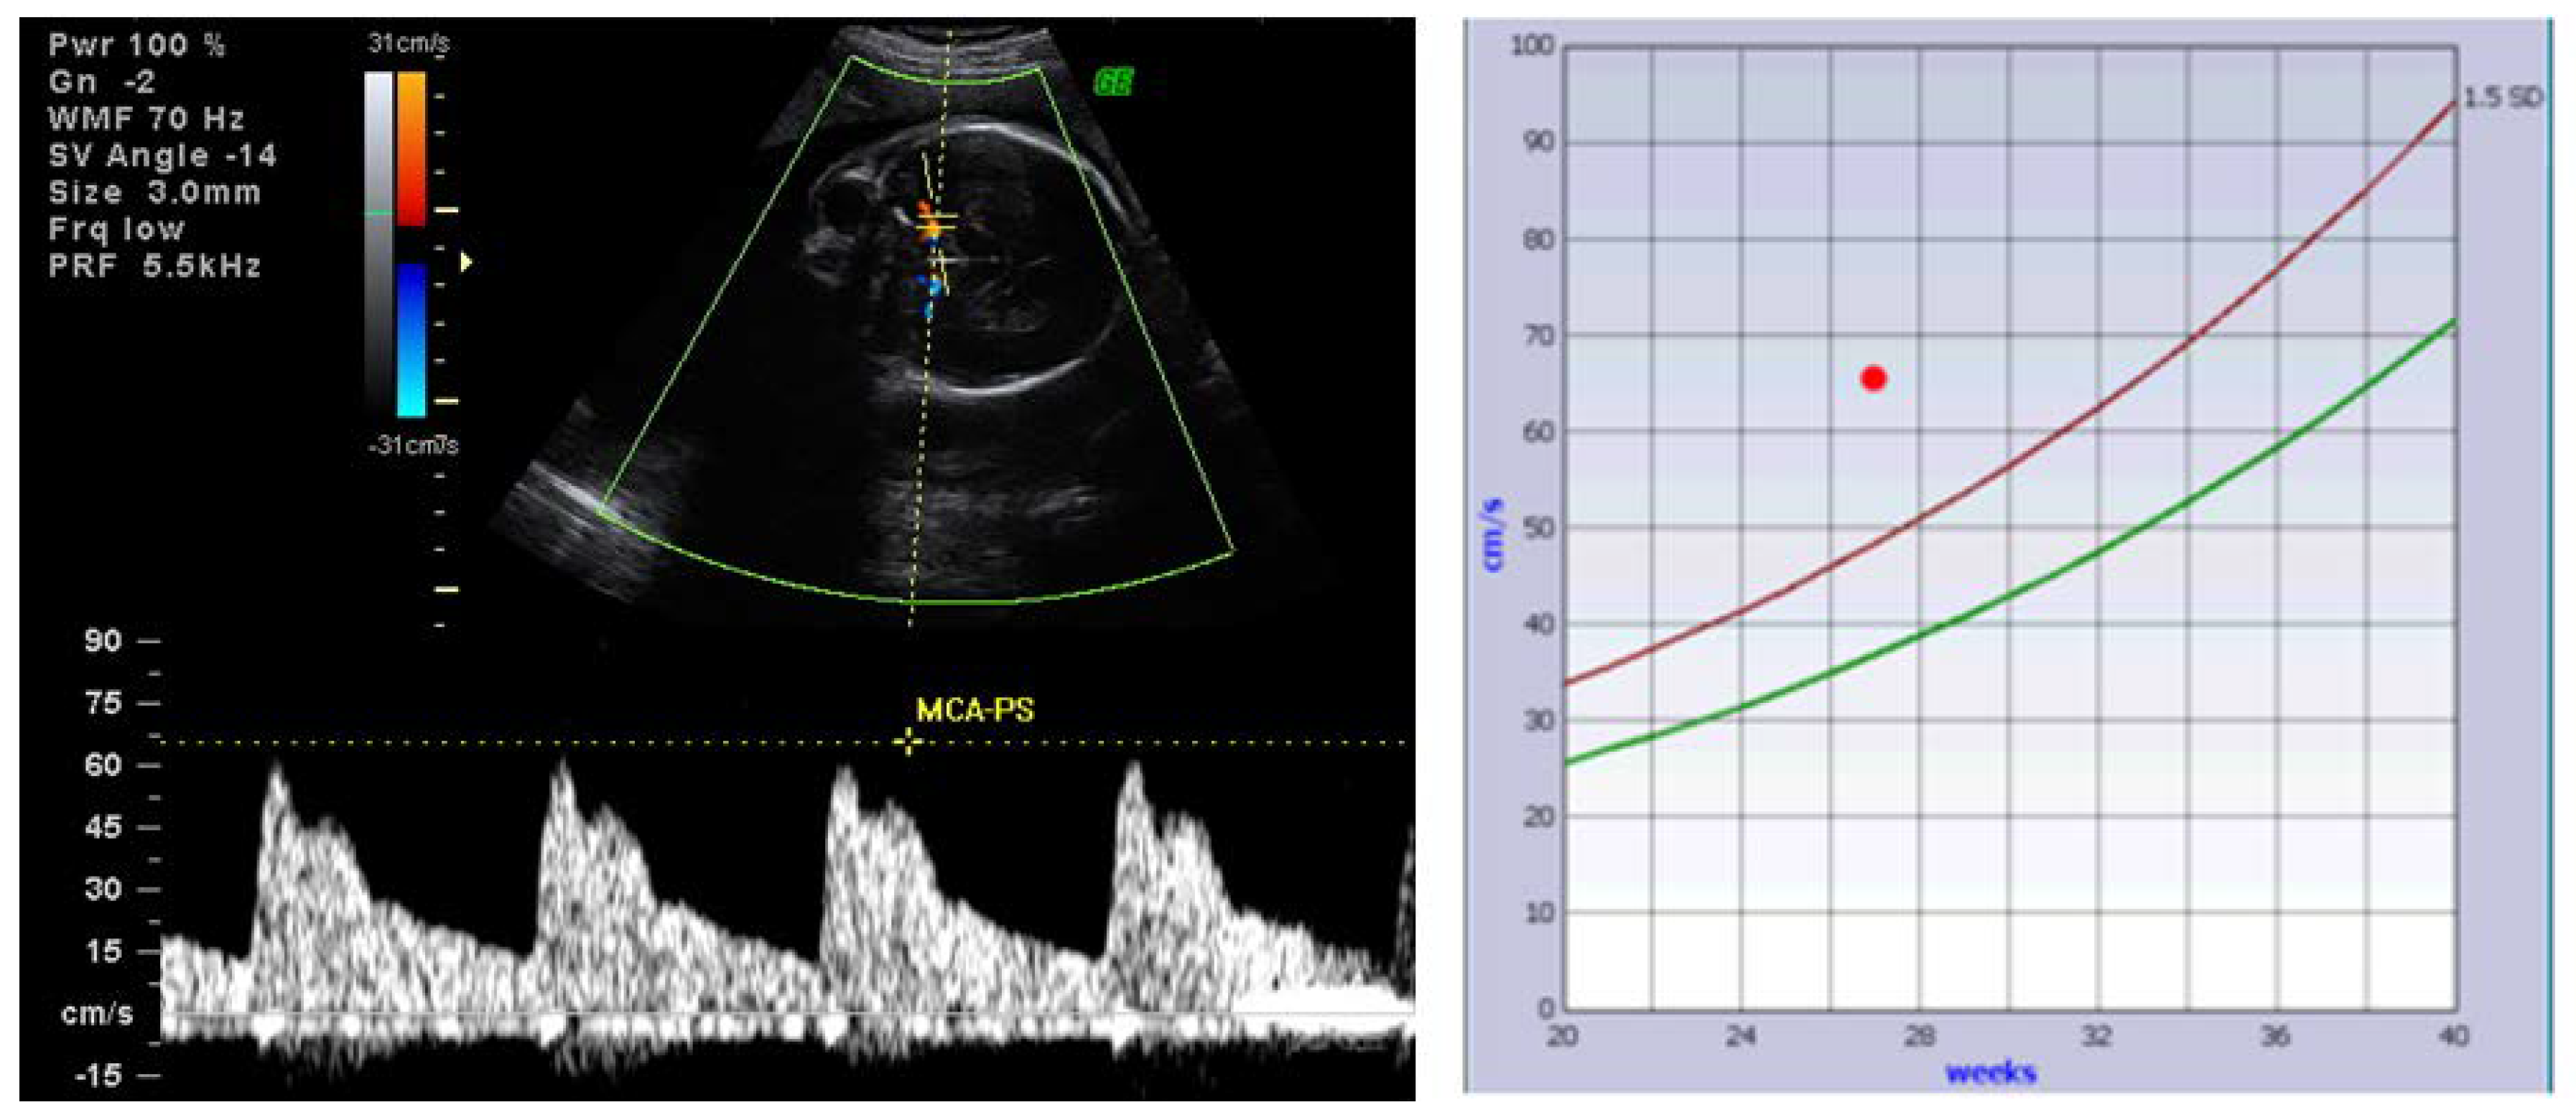

- Huel, C.; Guibourdenche, J.; Vuillard, E.; Ouahba, J.; Piketty, M.; Oury, J.F.; Luton, D. Use of ultrasound to distinguish between fetal hyperthyroidism and hypothyroidism on discovery of a goiter. Ultrasound Obstet. Gynecol. 2009, 33, 412–420. [Google Scholar] [CrossRef] [PubMed]

- Panaitescu, A.; Nicolaides, K. Fetal Goitre in Maternal Graves’ Disease. Acta Endocrinol. (Buchar.) 2018, 14, 85–89. [Google Scholar] [CrossRef]